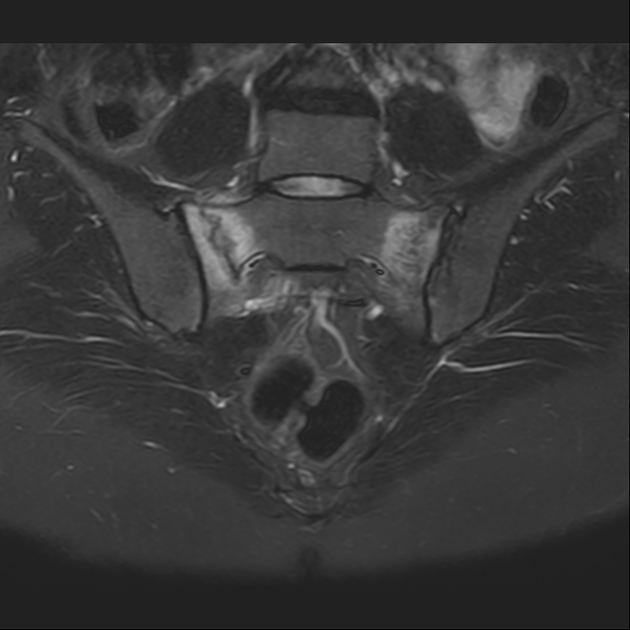

STIR

6、磁共振上可以发现骨折线周边明显的骨髓水肿,增强扫描明显强化

磁共振影像表现